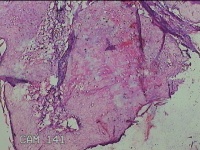

右侧腰臀部包块

性别

女

年龄

44岁

临床诊断

臀部良性肿瘤

一般病史

发现右侧腰臀部包块1个月余。

标本名称

大体所见

灰白粉红色包块0.8x0.3x0.2cm一个,表面光滑。

良性病变。